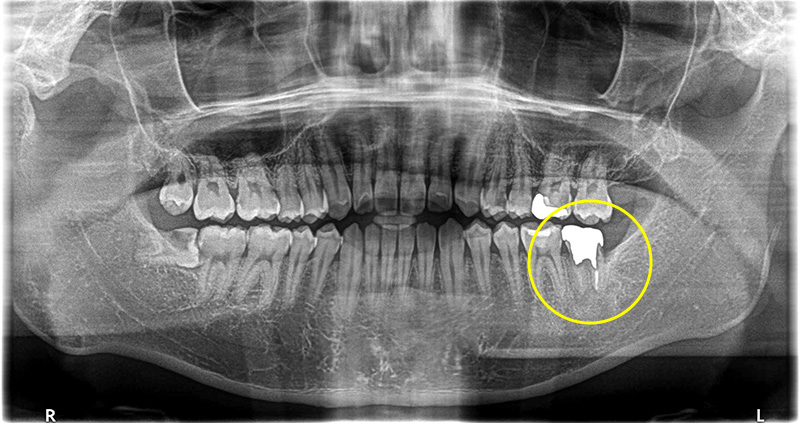

当院では1000本を超えるインプラント治療の実績に基づき、CTによる精密な診断のもと、安全性を優先した治療計画を立案します。 骨造成など難度の高い症例にも対応可能です。 失われた歯の機能と見た目を取り戻すための、良質な方法をご提案します。